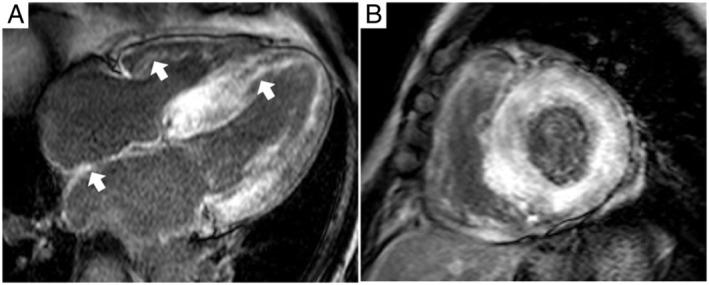

Wild-type transthyretin amyloid cardiomyopathy (ATTRwt-CM) is caused by the deposition of wild-type transthyretin (TTR) amyloid fibrils in the heart. The age at diagnosis of ATTRwt-CM is reported to be approximately 70-80 years, and patients commonly present with non-disease-specific cardiac abnormalities, such as heart failure with preserved ejection fraction and diastolic dysfunction. The disease can be fatal if left untreated, with an approximate survival of 3-5 years from diagnosis. An oral TTR stabilizer, tafamidis, has enabled early intervention for the treatment of ATTRwt-CM. However, awareness of ATTRwt-CM remains low, and misdiagnosis and a delay in diagnosis are common. This review discusses the epidemiology, characteristics, treatment strategy, and red-flag symptoms and signs of ATTRwt-CM based on the published literature, as well as recent advances in diagnostic modalities that enable early and accurate diagnosis of the disease. We also discuss an algorithm for early and accurate diagnosis of ATTRwt-CM in daily clinical practice. In our diagnostic algorithm, a suspected diagnosis of ATTRwt-CM should be triggered by unexplained left ventricular hypertrophy (LVH), which is LVH that cannot be explained by an increased afterload due to hypertension or valvular disease. In addition, heart failure symptoms, laboratory test results (N-terminal pro-B-type natriuretic peptide, high-sensitivity troponin T, or high-sensitivity troponin I), electrocardiogram and imaging (echocardiogram or cardiac magnetic resonance) data, age (≥60 years), and medical history suggestive of ATTRwt-CM (e.g. carpal tunnel syndrome) should be examined. Detailed examinations using bone scintigraphy and monoclonal protein detection tests followed by tissue biopsy, amyloid typing, and TTR genetic testing are warranted for a definite diagnosis of ATTRwt-CM.